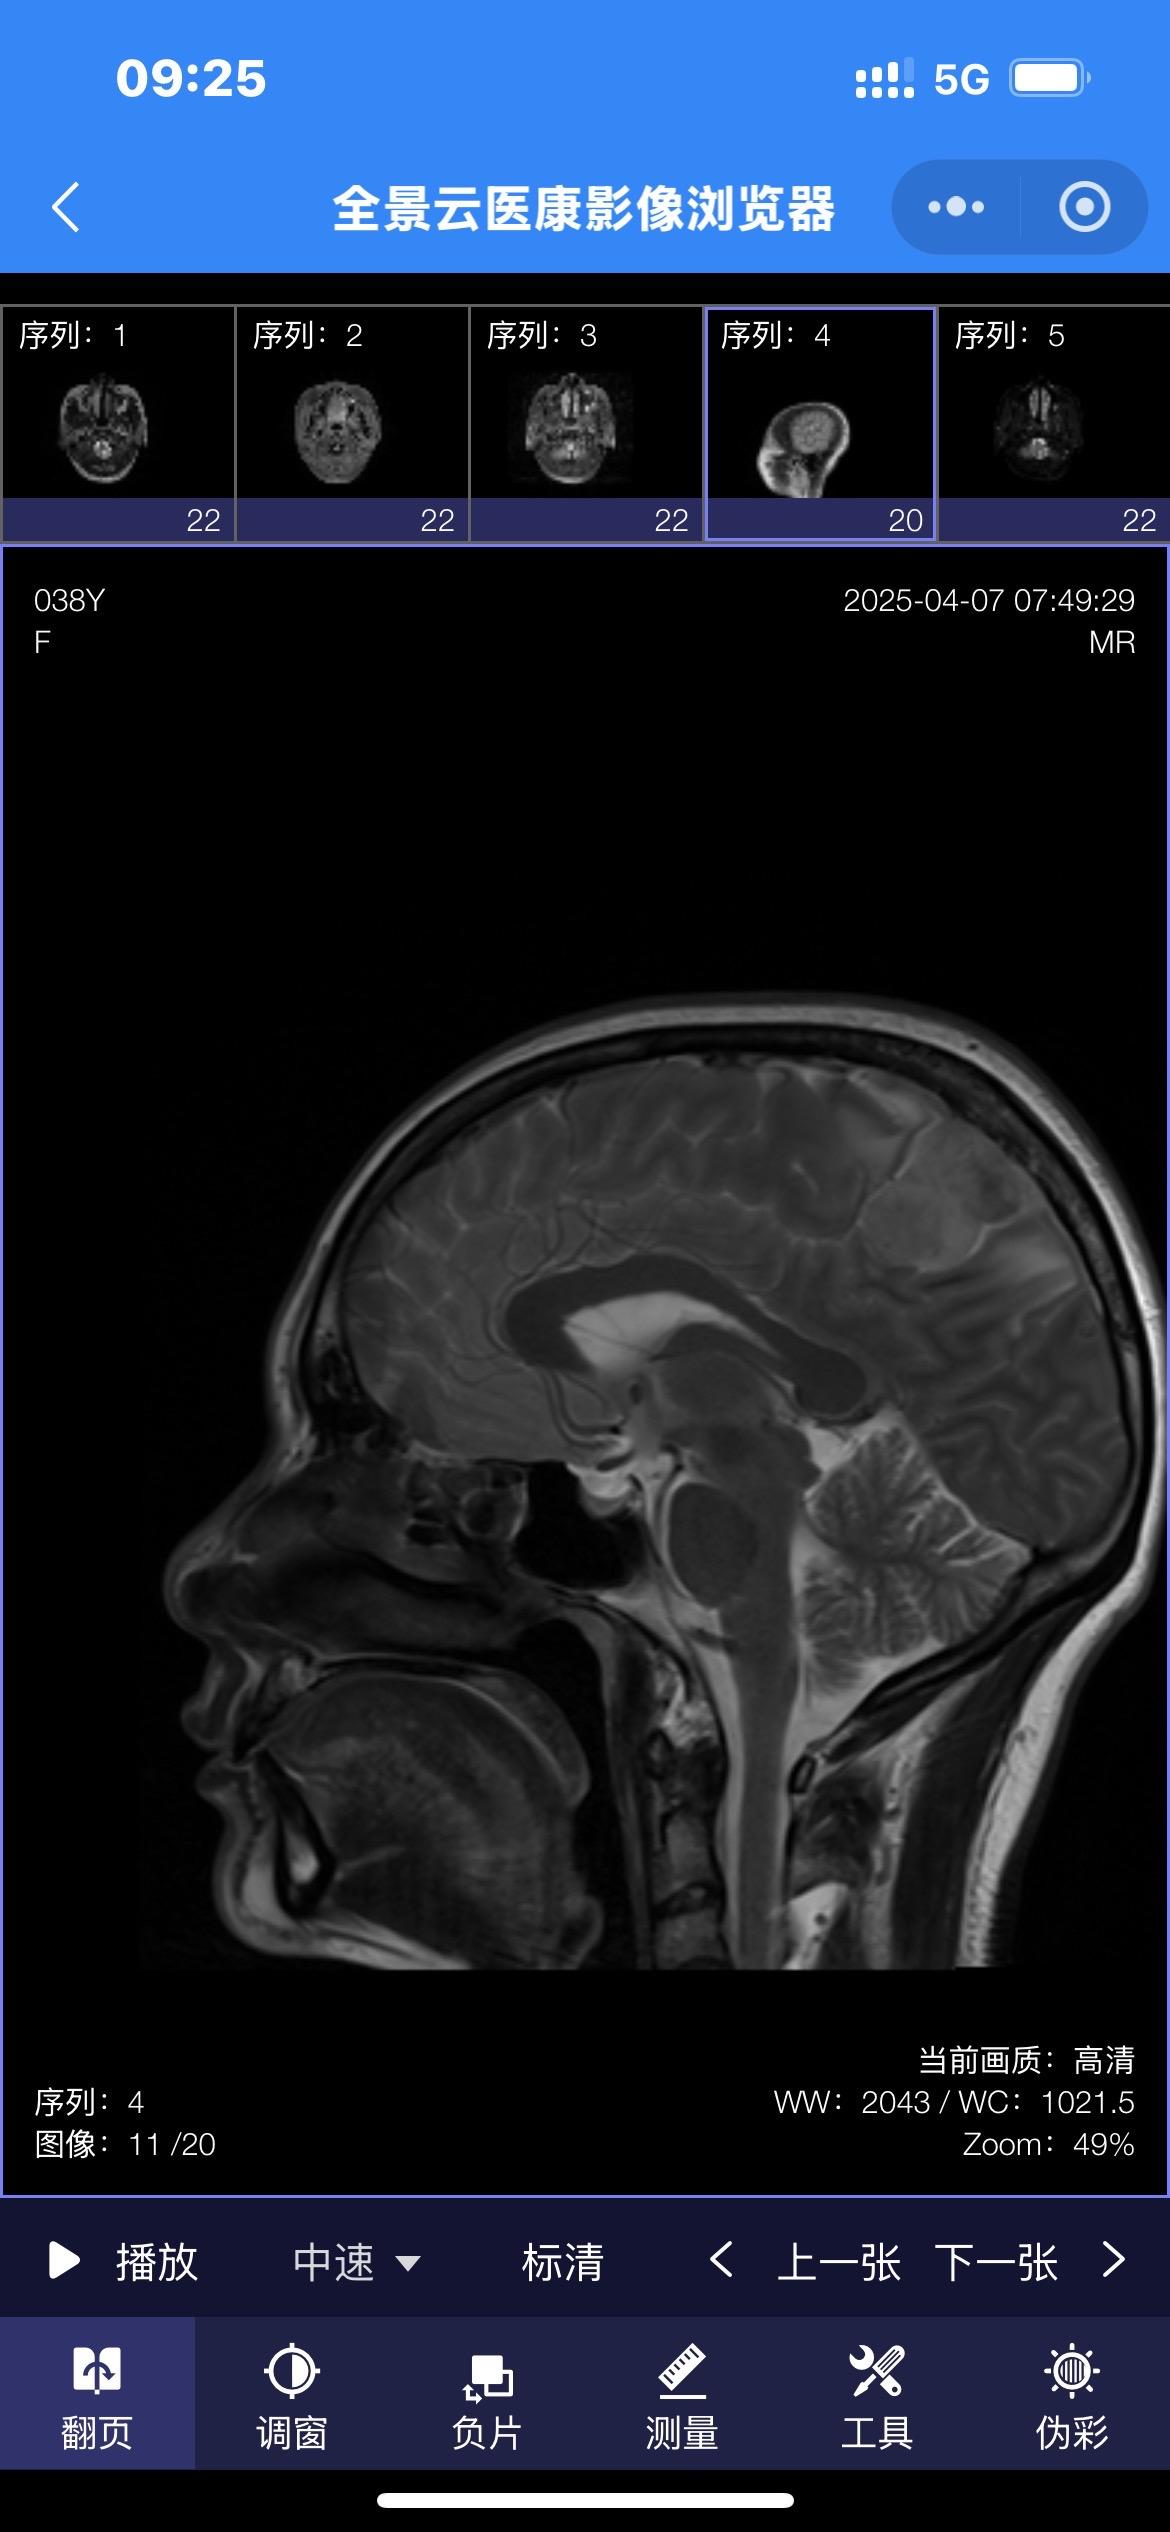

38岁女性因头痛发现脑膜瘤。脑膜瘤在女性的发病率要高于男性! 首选的治疗方法就是切除肿瘤。 有的脑膜瘤切除的难度不大,有的脑膜瘤却是难以切除干净的。 这个脑膜瘤位置就不太好,位于中央区(有重要的功能的区域),切除难度就很大!脑膜瘤手术